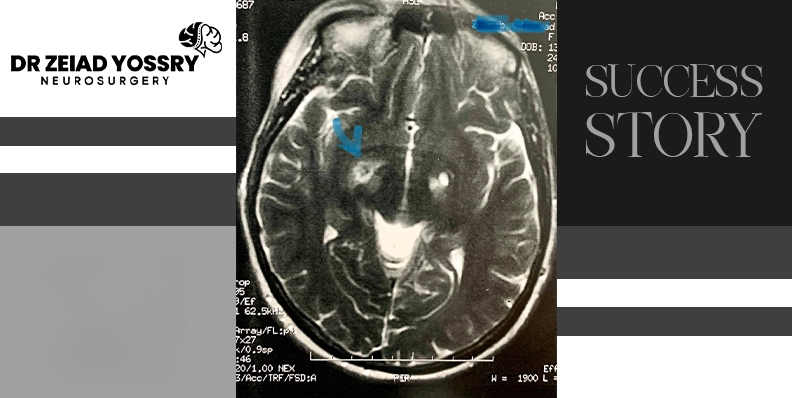

Dr. Zeiad Yossry performed basal ganglion ablation surgery, which involves targeting the globus pallidus. This area is responsible for the symptoms of Parkinson's disease. The surgery reduces its activity, helping to reduce tremors and slow movement symptoms. During the procedure, the medical team placed a frame to stabilize her head, and Dr. Zeiad Yossry determined a precise path using CT scans. After sterilizing the scalp, he made a tiny incision to insert electrodes used to stimulate the brain and monitor changes in symptoms. Once reaching the target area, Dr. Zeiad Yossry applied precise thermal energy to ablate the basal ganglion. Finally, he performed an MRI scan to confirm successful symptom control.